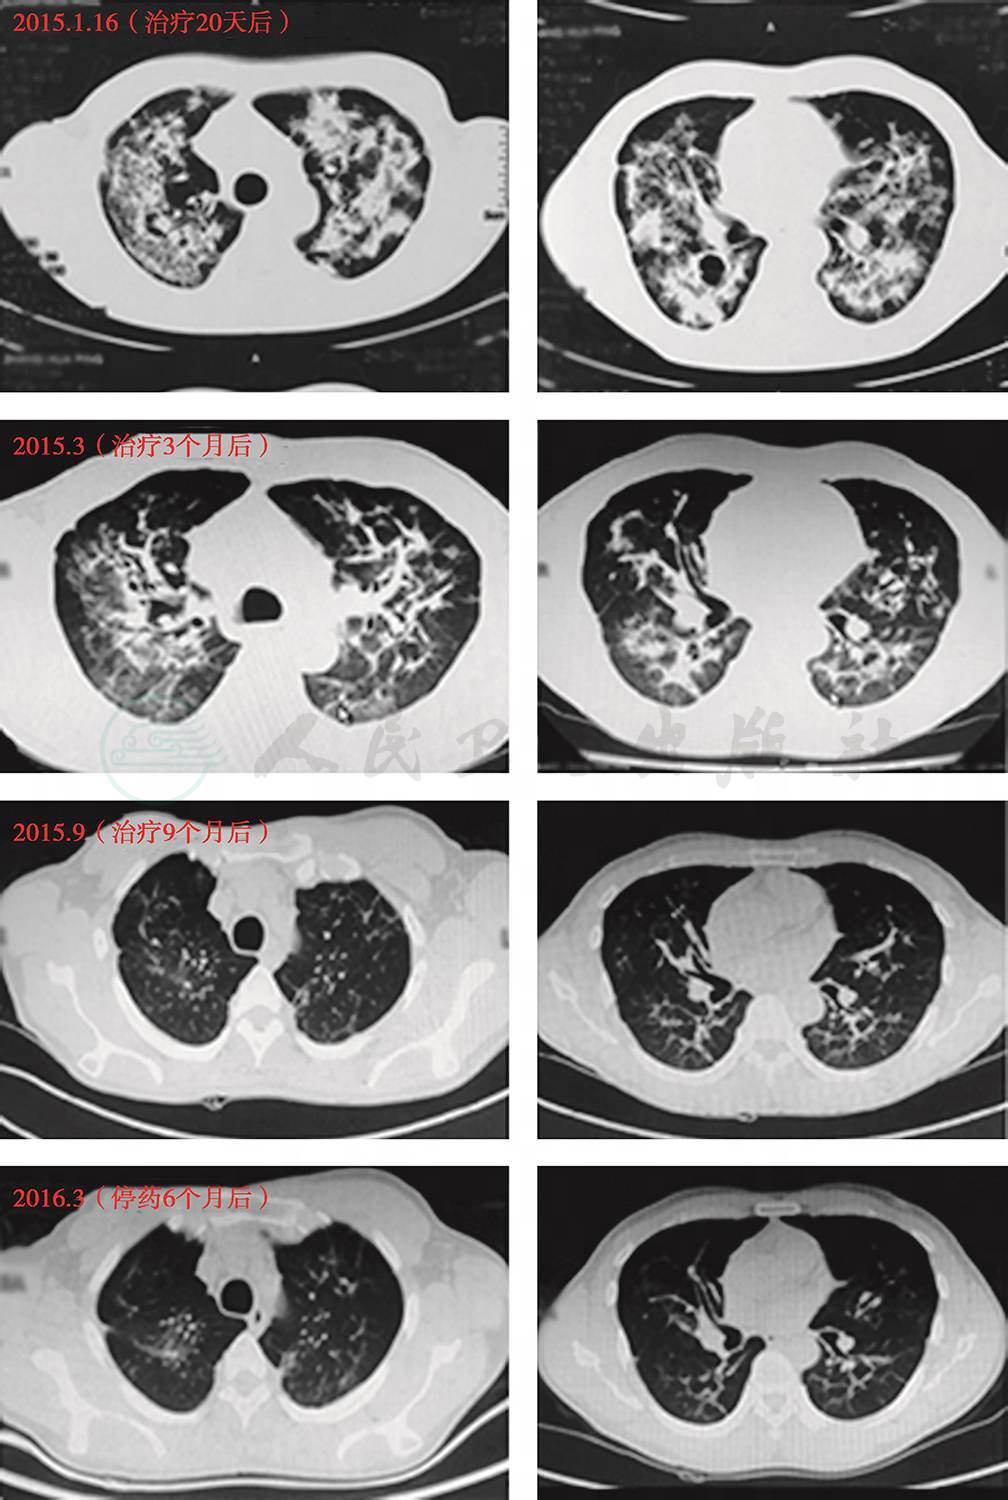

(二)随访

患者抗真菌治疗后,咳嗽、呼吸困难等症状明显缓解,肺部影像学病变明显好转(图6)。随访4年,患者除仍有轻微咳嗽外,无其他呼吸道相关症状。

图6 出院后随访CT

(CT时间包括2015年1月、2015年3月、2015年9月、2016年3月、2017年3月、2019年3月)